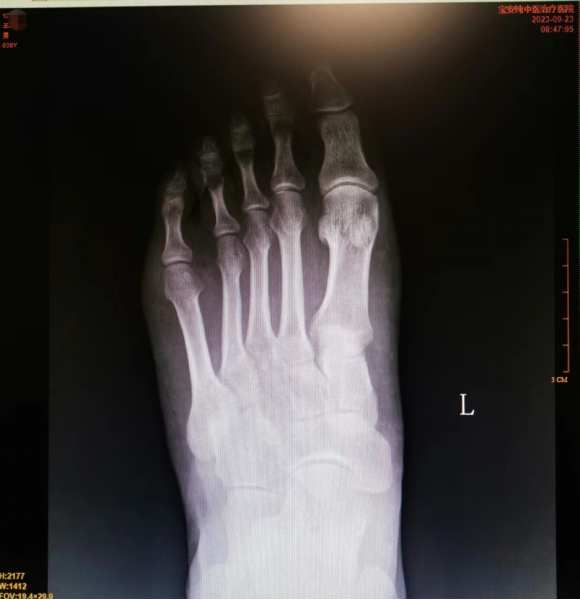

辅助检查:2023-09-23我院右侧足部正斜位片:左足第3跖骨体、第4跖骨基底部骨质密度不均,内见线状影周围骨质密度增高,余足部诸骨骨质未见异常。 考虑左足第3、4跖骨陈旧性骨折,请结合临床病史。

诊断:1、左第3跖骨体陈旧性骨折 2、左第4跖骨基底部陈旧性骨折